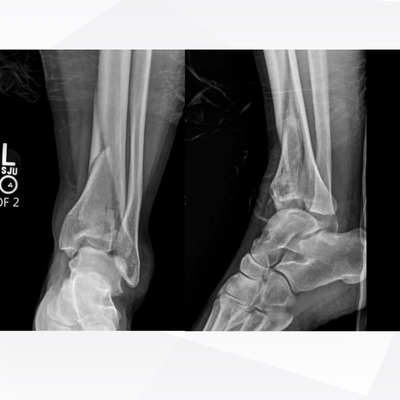

Click on an image below to view more info.